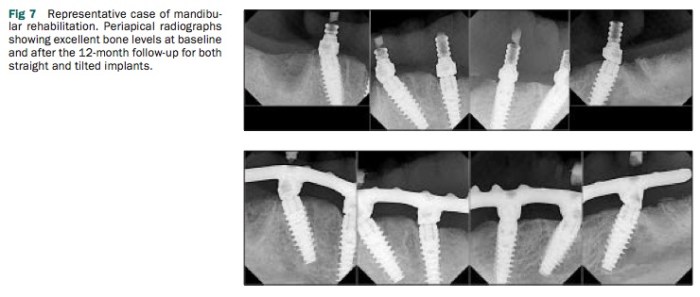

這個retrospective cohort study,是使用Nobel Biocare原廠的設計, 用Nobel Active加上internal connection multiunit abutment, 在同一院所的169位患者(856支植體)中追蹤marginal bone loss至少一年.

這篇追蹤的研究其結果跟Dr. Malo聲稱的很接近, 成功率高(99.8%survival rate), bone loss大約到第一螺紋(1mm), 所以這樣all-on-4的方式, 在使用Nobel Active這類的tapered platform-shift式的植體是目前我看到目前的趨勢. 但是你一定要用Active?這見人見智…